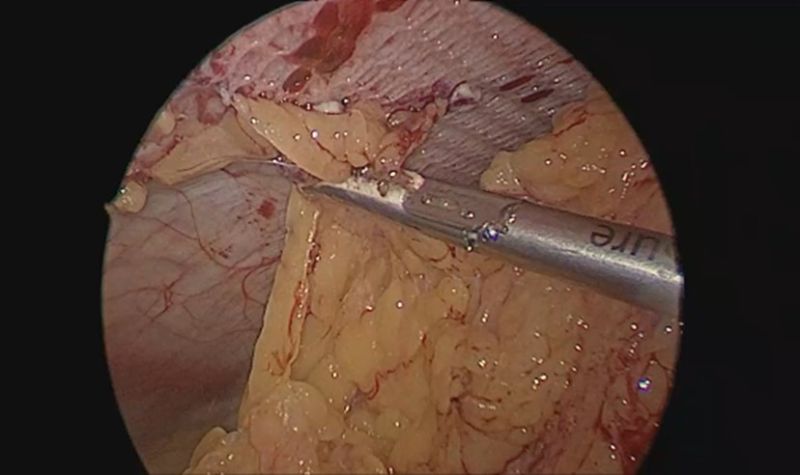

Plain CT scan of the abdomen was done that revealed a 3.1 cm sized defect in the anterior abdominal wall along the left lateral lumbar region with omentum and bowel loops as hernial contents. A diagnosis of trocar site incisional hernia (TSIH) was made, and the patient was planned for laparoscopic IPOM for the left lumbar hernia. Patient was placed in the supine position with a slight right tilt arms tucked by the side. Pneumoperitoneum was created using a Veress needle at the palmer’s point. Optical view entry using a 5mm optical trocar was done at the right hypochondrium, then a right iliac 5mm port and another 10mm port in the right lumbar region were placed under vision for instrumentation (figure 1). Adhesions were visualized over the previous mesh and adhesiolysis was performed. A defect in left lumbar region was seen, and it was approximated using absorbable barbed sutures in a continuous fashion. A 15x15 composite mesh was placed over the defect with a margin of 5 cm on either side. The defect was seen to be overlying on the previous mesh. Mesh was sutured using absorbable barbed sutures and inner crowning of the mesh was done using absorbable tacks. TAP block was given laparoscopically and proper haemostasis was achieved. 10mm port site was closed using a non-absorbable figure-of-8 stitch. Patient was shifted to ward, and she was managed with intravenous analgesics, antibiotics as well as antacids. Visual analogue scale (VAS) score for pain on post-operative day-1 was 3 out of 10. The patient recovered well after the procedure and was discharged in a hemodynamically stable state on post-operative day 2.

Figure 2: Omental adhesions over the previous mesh